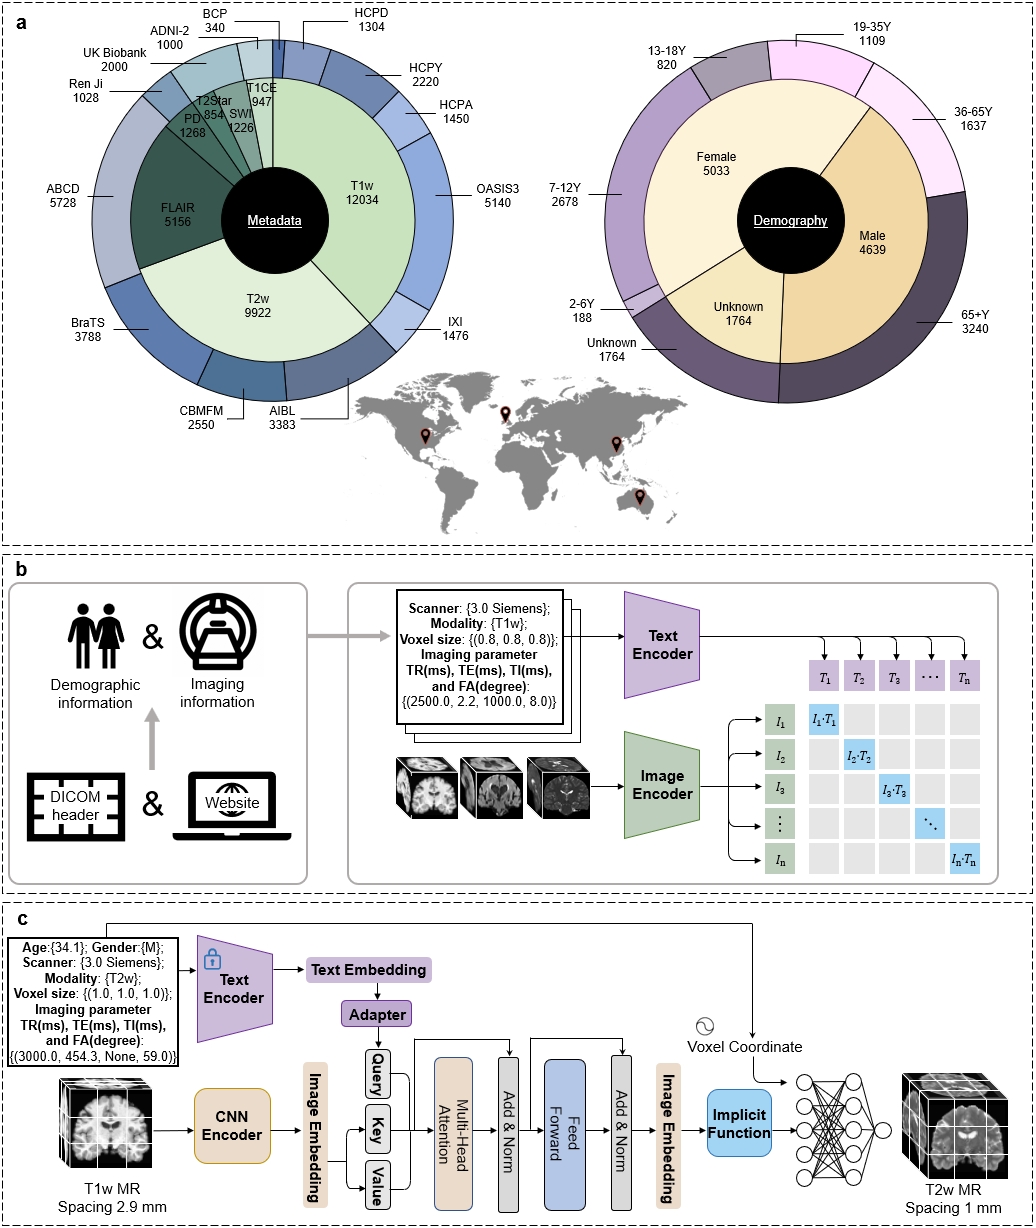

In this work, we present the Text-guided Universal MR image Synthesis (TUMSyn) framework, designed to generate customized MRI sequences from routinely-acquired scans based on text prompts (Fig. 1). TUMSyn is developed using a large database of 31,407 MR image-text pairs from 13 datasets (Table 1). To allow customized synthesis of MRI sequences, we pre-train a text encoder to extract embeddings of MR imaging parameters as prompts and align these text embeddings with the corresponding images using the CLIP approach.We have conducted comprehensive evaluations across a wide range of cross-modal synthesis tasks. TUMSyn consistently surpasses the models trained for specific tasks. In addition to promising synthesis performance on internal data, evaluation on four external datasets further demonstrates the generalizability of TUMSyn. Notably, in zero-shot settings, radiologists’ assessments and various evaluation metrics indicate that TUMSyn produces high-fidelity sequences that can meet diverse clinical and research needs, assisting neuro-disease diagnosis and also facilitating brain morphological analysis. In summary, guided by text prompts, TUMSyn enables multimodal imaging by effectively generating MRI sequences that are difficult or impossible to acquire in reality, providing the potential to significantly augment the efficiency and efficacy of the healthcare system.

Text-guided universal framework for brain MRI synthesis

The overview of our work is shown in Fig.1. The goal of our work is to develop a universal synthesis framework for brain MR images, which can generate desired high-quality MR images according to practical demands provided by text prompts. To ensure the versatility and generalizability of our synthesis model, we collected a large-scale brain MR database with 31,407 3D image-text pairs from 13 datasets located in four continents, including 7 structural MRI modalities, spanning ages from 2 to 100+ years old, and covering a large spectrum of diseases and health conditions (Table 1). The text (metadata) includes subject information such as age and gender, as well as key MR imaging parameters, including scanning field strength, scanner type, voxel size, repetition time (TR), echo time (TE), inversion time (TI), and flip angle (FA). The designed English prompt integrates metadata as illustrated in Fig.1 b and c. To effectively align and fuse image-text pairs, our TUMSyn is built upon a two-stage training strategy. In the first stage, we pre-trained a text encoder using contrastive learning to effectively extract textual semantic features which are aligned with the corresponding image features from metadata (Fig.1 b). In Supplementary Fig.1 a and b, we evaluate the pre-trained text encoder by showing zero-shot performance on image-to-text retrieval. We can see that our text encoder accurately provides highly relevant textual descriptions for the given images, either producing complete prompts or solely imaging modality, indicating its ability to understand and master the semantic relationship between paired images and texts. More details are given in section “Description of experimental setup”.

Built on the pre-trained text encoder, in the second stage, the text encoder is frozen and used to extract prompt features to steer the cross-sequence synthesis. To enable MRI synthesis with desired spatial resolution, the fused text and image features are passed to a decoder, which supports super-resolution for continuous upsampling factor using Local Implicit Image Function (LIIF) [26]. In such way, our model, developed on large-scale datasets, can effectively generate target sequences with desired spatial resolution (Fig.1 c).

To establish a large-scale brain MRI dataset, we collected 31,407 3D scans of 12,487 individuals from diverse institutions around the world spanning ages from 2 to 100+ years old across four continents, including Open Access Series of Imaging Studies (OASIS) [33], Human Connectome Project (HCP) [34], IXI [35], Australian Imaging Biomarker and Lifestyle (AIBL) [36], Brain Tumor Segmentation (BraTS) Challenge 2021 [37], Chinese Brain Molecular and Functional Mapping (CBMFM), Adolescent Brain Cognitive Development (ABCD) [38], UK Biobank [39], Ren Ji Hospital in Shanghai, and Alzheimer’s Disease Neuroimaging Initiative (ADNI) [40], where HCP includes HCP Development (HCPD), HCP Young Adult (HCPY), HCP Aging (HCPA), and Baby Connectome Project (BCP) [41]. The most commonly used MRI sequences in clinics are included such as T1w, T2w, FLAIR, SWI, T2 star, PD, and contrast-enhanced T1w (T1CE) images. Most data used for this study were obtained from publicly available research articles. For in-house datasets CBMFM and Ren Ji Hospital data, the institutional review board approved the retrospective analysis of internal brain MR images. All internal digital data, including MR images and demographic information, were de-identified before computational analysis and model development. Patients were not directly involved or recruited for the study. Informed consent was waived for analyzing MR images retrospectively. The detailed information of each dataset is presented in Table 1, and the scanning parameters along with the corresponding amount of scanns are summarized in Extended Data Fig. 1.

To encourage the model to accommodate practical scenarios from multi-center data, the preprocessing step is reasonably simplified to a minimal extent. First, we performed co-registration for each subject and then stripped skulls for each scan. No other operations were conducted. To utilize text prompts, we collected demographic information and imaging parameters including field strength, scanner model, voxel size, TR, TE, TI, and FA of each scan from DICOM header files and official websites of datasets. These imaging parameters control the contrast and resolution of the image during the real MR scanning process.

The model framework is demonstrated in Fig. 1 b and c, which contains two training stages: the language-image pre-training (shown in b) and the training of the image synthesis network (shown in c). More details are given below.